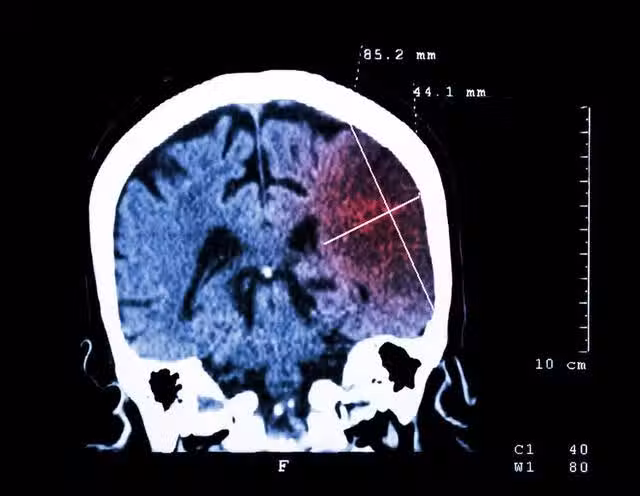

到院時,老莫已經出現斜視嘴和斜視眼的症狀,醫生初步診斷為突發腦梗,馬上對老莫進行急救。遺憾的是,由於情況嚴重,老莫永遠地閉上了眼睛,死於大面積腦血管堵塞。

醫生推測,可能是感冒惡化了老莫的原有疾病,冷風一吹,一直被耽誤治療的高血壓就突然爆發,誘發了腦梗塞,奪走了老莫的寶貴生命。